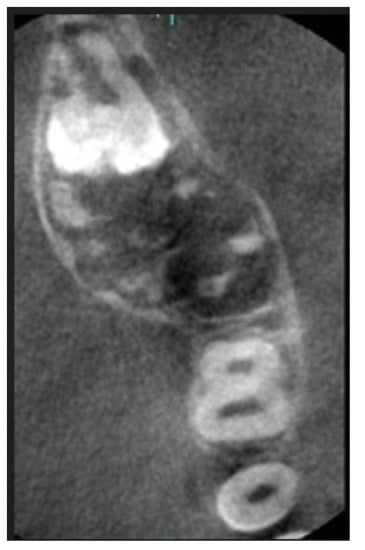

Treatment Possibilities in Mandibular Defect Reconstruction Based on Ameloblastic Fibro-Odontoma Treatment—Does Small Bone Defects Heal without Bone Grafting?

2. Case Report Presentation